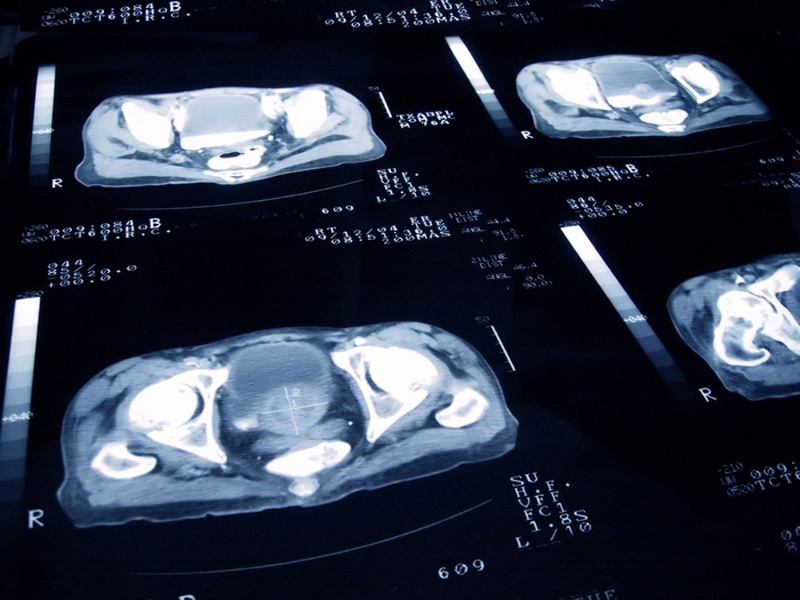

Il 10% degli uomini tra 40 e 50 anni soffre di Ipertrofia Prostatica Benigna (IPB), una patologia che prima era “riservata” alle età più avanzate (la prevalenza sfiora il 35% fra i 50-60enni), ma l'attività fisica protegge da questo problema. Lo afferma uno studio della Società Italiana di Urologia (SIU) pubblicato dall'Archivio Italiano di Urologia e Andrologia.

I dati sono stati raccolti a giugno-luglio 2017 in oltre 60 dei 173 centri che hanno aderito alla campagna #Controllati 2017, svolta dalla SIU con il supporto non condizionante di Menarini. L'indagine ha permesso di individuare per la prima volta i fattori di rischio associati allo sviluppo della malattia negli uomini italiani: avere la pressione alta per esempio incrementa la probabilità di IPB del 50%, il diabete la aumenta del 57%, colesterolo e trigliceridi alti fino al 37%. La sindrome metabolica, quando si è sovrappeso e tutti questi valori sono oltre la soglia anche se non troppo, raddoppia il rischio di IPB mentre fumare più di dieci sigarette al giorno alza la probabilità del 57%.